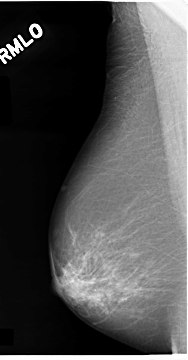

C_0074_1.RIGHT_MLO

LEFT_MLO LINES 4704 PIXELS_PER_LINE 2552 BITS_PER_PIXEL 12 RESOLUTION 50 OVERLAY

FILE: C_0074_1.LEFT_MLO.OVERLAY

TOTAL_ABNORMALITIES 1

ABNORMALITY 1

LESION_TYPE MASS SHAPE IRREGULAR MARGINS SPICULATED

ASSESSMENT 5

SUBTLETY 5

PATHOLOGY MALIGNANT